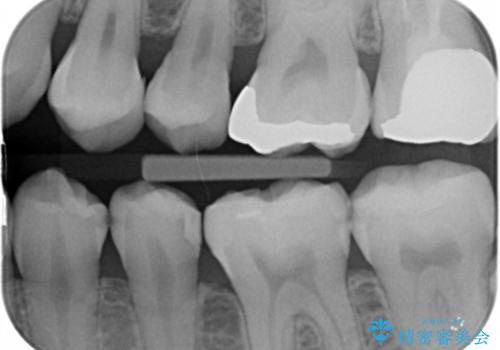

- 定期検診で来院してレントゲンを撮ったところ

歯と歯の間にう蝕ができていました。

拡大鏡下でう蝕を全て除去してe-maxインレーにて治療を行いました。